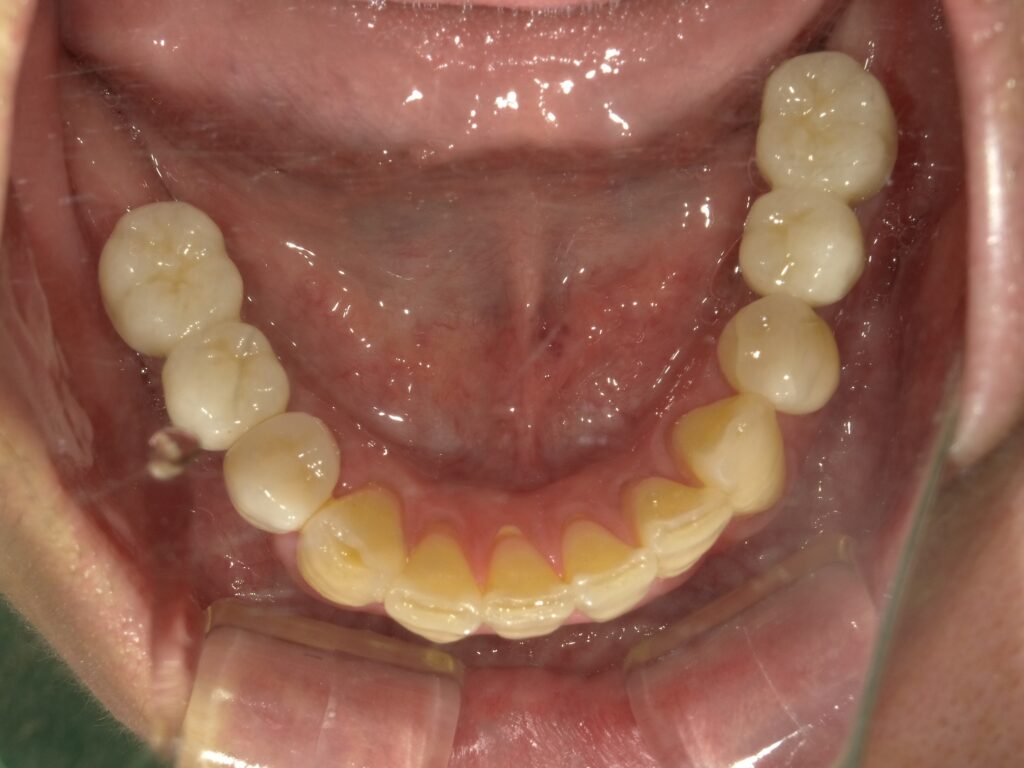

BEFORE

AFTER

主訴

全体的に見た目を綺麗にしたい。奥歯でしっかり噛みたい。

診断名・主な症状

臼歯部欠損

年齢

65歳

治療内容

インプラント埋入(左下5・6,右下5・6,左上4・6)

サイナスリフト(左上4・6)

ジルコニアBr(右上6−左上3)

E –MAX CAD(右下4)

セラミックインレー(左下4)

治療期間/

通院回数

約1.5年/約20回

費用

インプラント治療 約2,000,000円

その他被せ物治療など 約1,000,000円

合計 約3,000,000円

*いずれも税込